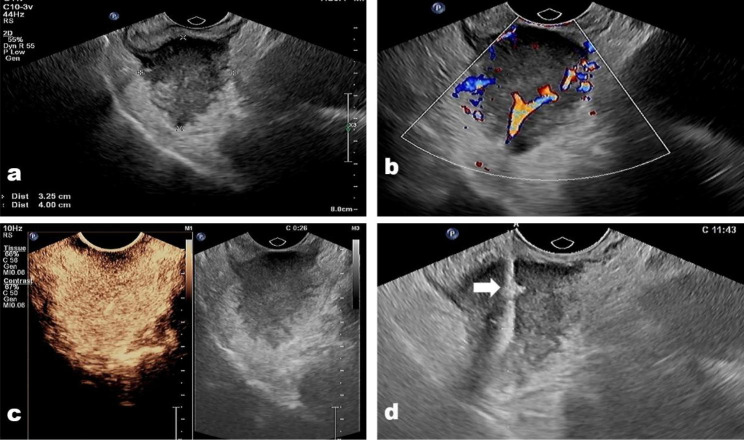

Fig. 1.

(a) A neuroendocrine neoplasm located in the lower rectum in a 51-year-old man. (b) The tumor showed abundant vascular on color Doppler image; (c) the tumor presented hyper-enhanced on contrast-enhanced condition, and there was no necrosis area in the tumor. (d) The biopsy needle (arrow) passes through the tumor center to acquire biopsy samples